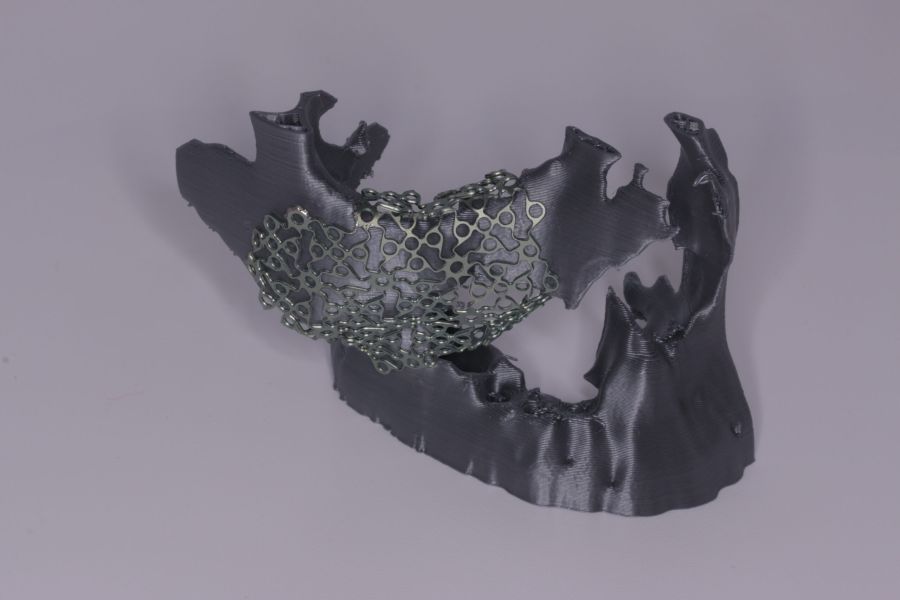

Presentamos el caso de una paciente de 47 años que acude al servicio de cirugía maxilofacial por dolor en el área sinusal derecha en Junio de 2020. Se realizó una radiografía panorámica en la que se observó una imagen sospechosa en la zona del primer cuadrante. Dichos hallazgos se confirmaron con la realización de una tomografía axial computarizada (TAC) facial y una resonancia magnética en las que se identifica una extensa lesión tumoral que ocupaba el seno maxilar derecho e infiltraba el suelo de la órbita derecha y fosa nasal derecha (Figuras 1, 2 y 3). Tras la realización de una biopsia, se confirmó la presencia de un carcinoma adenoide quístico. De este modo, se planificó la extirpación quirúrgica y la fijación mediante placas preformadas sobre un modelo impreso en poliamida (Figura 4).

Bajo anestesia general, se realizó la resección quirúrgica junto con la fijación de dos placas preformadas y colocación simultánea de dos implantes cigomáticos y un implante endoóseo en posición del 2.1 (Figuras 5 y 6). Debido a la presencia de márgenes quirúrgicos comprometidos en el informe anatomopatológico, se indicó la administración de radioterapia adyuvante. Por este motivo, se decidió realizar un puente provisional dentosoportado de 1.7 a 2.3 (Figura 7) para mejorar la situación estética y funcional de la paciente durante todo el proceso y evitar un colapso de los tejidos blandos por la radioterapia. Para ello, se tallaron los molares (1.7, 1.6) e incisivo lateral y canino (2.2, 2.3), y se fabricó un puente fresado en polimetilmetacrilato (PMMA) con refuerzo metálico (Figuras 8 y 9).